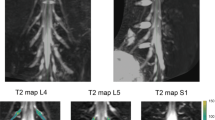

Image segmentation was performed manually in FSLview (https://www.fmrib.ox.ac.uk/fsl/) using the SHINKEI images. For each lumbar segment (L2-L5), annotated binary masks were used to distinguish between preganglionic, ganglionic and postganglionic regions of similar volume (Fig. 2C,D). All MTR volumes were subsequently co-registered to their respective SHINKEI volumes using affine registration with NiftyReg22. Binary annotated masks were resampled applying the affine transformation and using nearest-neighbor interpolation in order to obtain segment- and region-specific MTR values (Fig. 3).

(A) Example of a magnetisation transfer ratio (MTR) map calculated in one healthy volunteer; (B) each MTR map was registered to the respective ‘nerve-SHeath signal increased with INKed rest-tissue RARE Imaging’ (SHINKEI) volume with annotated binary masks subsequently applied to obtain MTR values for each lumbar segment (only L2, L3, L4 shown here) as well as the preganglionic, ganglionic and postganglionic regions.